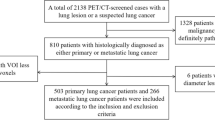

We validated the proposed method using 100 cases of PET/CT images that were obtained during a cancer-screening program. The detection performance was assessed by free-response receiver operating characteristic (FROC) analysis. The sensitivity was 83.0 % with the number of false positives/case at 5.0, and it was 8 % higher than the sensitivity of independent detection systems using CT or PET images alone.